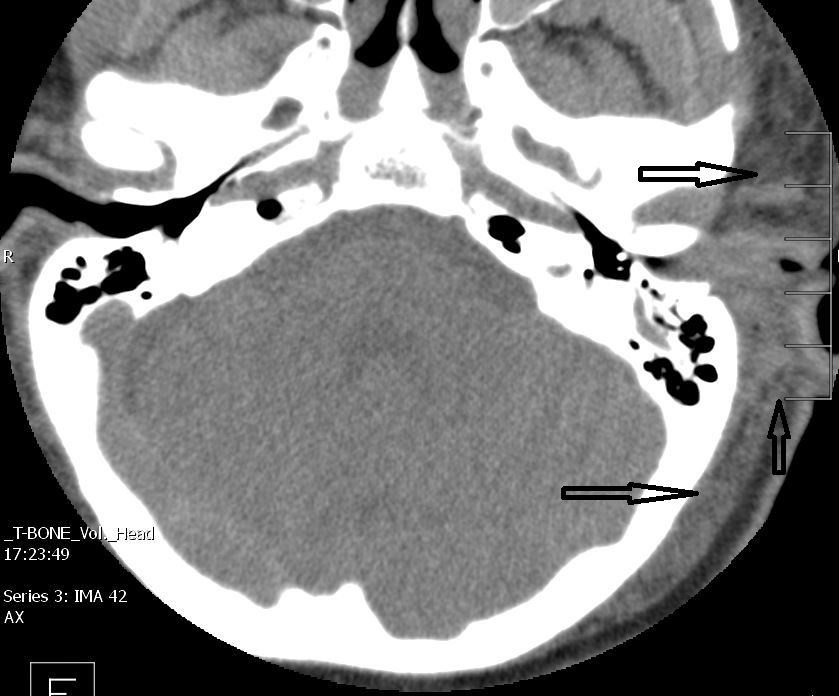

The inner ear including the lateral semicircular canals, vestibule and/or cochlea is fractured or otherwise abnormal. [Yes/No]

There is air within the membranous labyrinth. [Yes/No]

There is petrous apex fracture involving the IAC (and possibly injuring the 7th and 8th nerve), carotid canal and/or Eustachian tube. [Yes/No]

There is a fracture crossing the transverse sinus. [Yes/No]